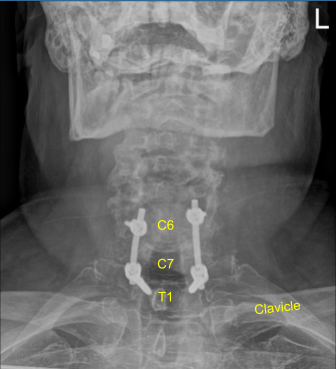

Image-guided stereotactic frame with neuronavigation techniques were used to place the instrumentation. We placed bilateral T1 pedicle screws and decorticated with electric high-speed drill cannulating with the navigated pedicle finder, palpating for breaches, measuring the depths, under tapping by 11 mm and placing 30 mm x 5.0 mm titanium pedicle screws bilaterally without difficulty.

Next, we placed bilateral lateral mass screws at C6. Inspecting the deformity of the spine, a decision was made not to place the C5 lateral mass screws because of kyphotic deformity and difficulty with rod placement.

So, we next decorticated the joints at C6-C7 and C7-T1 and bilateral T1 transverse processes with electric high-speed drill for the arthrodesis. The autograft resected was morselized. Precut-precontoured titanium rods were placed across the tulips from C6 to T1 and secured with locking caps and then final tightened with a torque and anti-torque device.

Morselized autograft and demineralized bone matrix allograft was packed in lateral gutters from C6 to T1 bilaterally. The wound was irrigated copiously until clear. Hemostasis was confirmed.